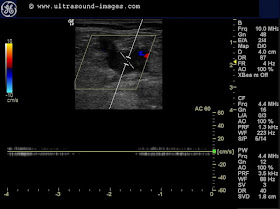

This is what we found when we did the colour Doppler study of the left lower limb.

This patient did not have any major pain or tenderness in the thigh.Clinically, he did not have features of deep vein thrombosis. Would you think of this possibility from these Doppler ultrasound images?

The answer: this is a case of Left femoral vein thrombosis. There is near total absence of flow signal in a major part of the left femoral vein. The lack of symptoms is explained by the patient having had anticoagulant treatment for a few days.